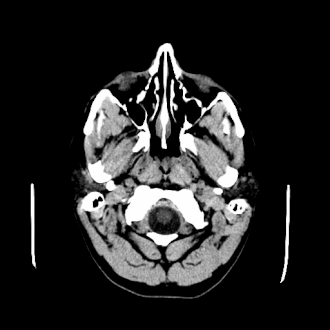

A CT scan of an arachnoid cyst

The diagnostic process typically begins with a medical history workup followed by a medical examination by a physician. Imaging tests, such as CT scans and MRIs, help provide a clearer picture. The physician typically looks for fluid (or other bodily substance) filled sacs to appear in the scans, as is shown in the CT scan of a colloid cyst. A primary health care provider will refer an individual to a neurologist or neurosurgeon for further examination. Other diagnostic methods include radiological examinations and macroscopic examinations. After a diagnosis has been made, immunohistochemistry may be used to differentiate between epithelial cysts and arachnoid cysts.[2] These examinations are useful to get a general idea of possible treatment options, but can be unsatisfactory to diagnose CNS cysts.[3][5] Professionals still do not fully understand how cysts form; however, analyzing the walls of different cyst types, using electron microscopes and light microscopes, has proven to be the best diagnostic tool. This has led to more accurate cyst classification and correct course of action for treatments that are cyst specific. In the past, before imaging scans or tests were available, medical professionals could only diagnose cysts via exploratory surgery.[2]